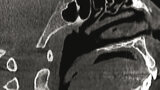

Význam 3D zobrazovacích systémů v současné ortodoncii